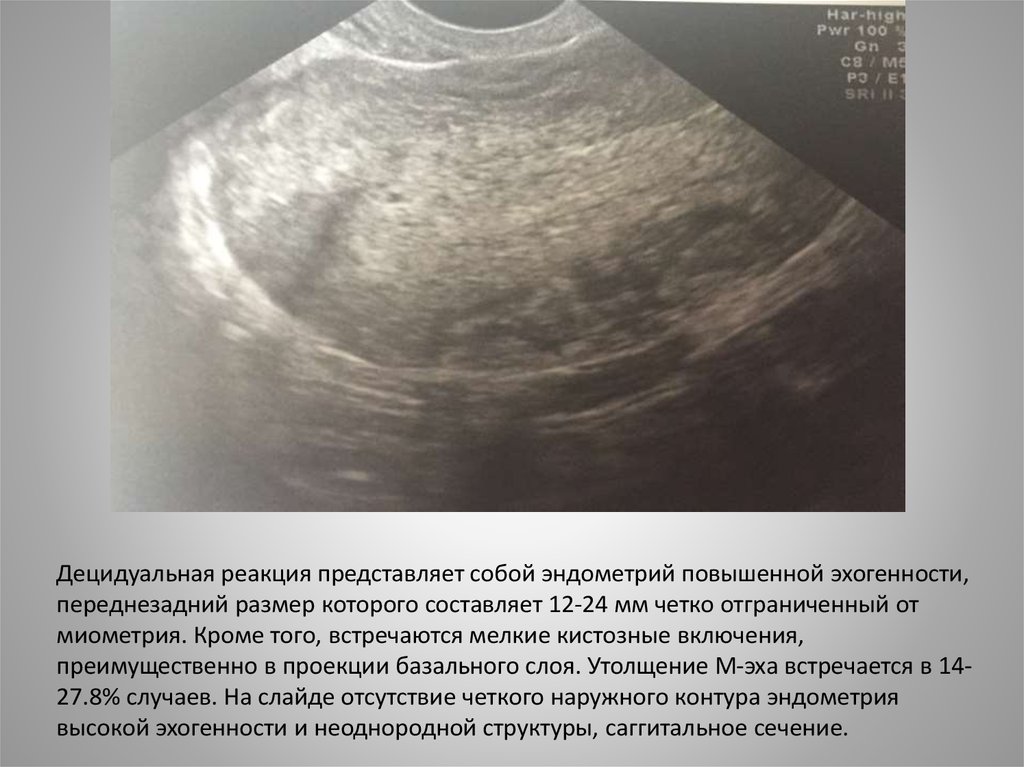

Раздел: Кадры перемен